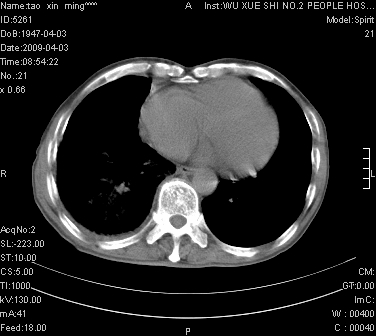

男.62.咯血.胸痛

是不是外伤的,看起来右侧肋骨骨折,右肺唑伤,右胸腔积血, 右肺背段可见一软组织肿块,边缘清晰,可以和中中央型肺ca合并

肺出血,周围型肺癌,右侧胸腔积液

明天请武大中南医院外科熊主任手术.患者无外伤.我考虑肺癌

右下周围型肺癌,右侧胸腔积。

右下周围型肺癌,右下肺出血,右侧胸腔积。

考虑肺癌并右侧胸腔积液肺出血

1)考虑右肺下叶周围型肺癌,并右肺下叶肺出血。2)右侧少量胸腔积液。

1)考虑右肺下叶周围型肺癌。2)右侧少量胸腔积液。